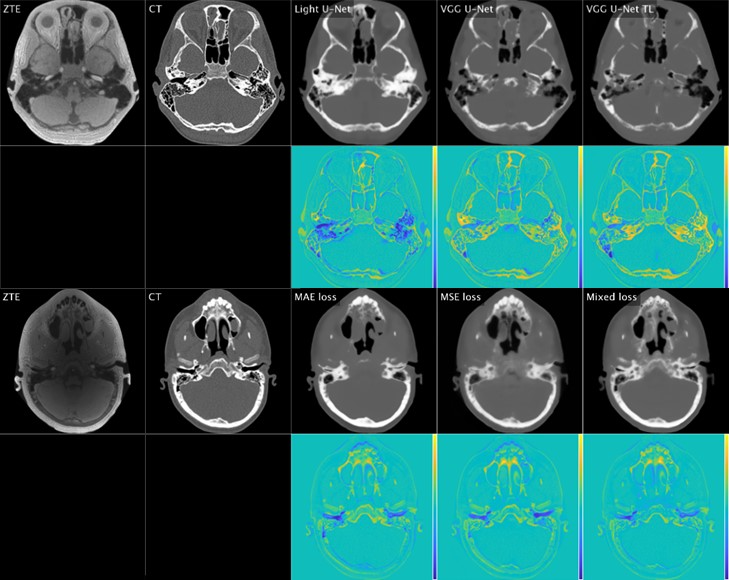

Comparison of ZTE, ground truth CT, and deep learning-generated synthetic CT [top rows] with color difference maps [bottom rows] for various neural networks and loss functions. Courtesy of Sven Bambach, PhD.

“We also experimented with different image processing approaches to generate synthetic CT or ‘bright-bone’ images from raw ‘black-bone’ ZTE data,” she said.

According to Dr. Ho, the group’s second aim was to compare the efficacy of both ZTE and CT for patient diagnosis and interventional planning. She noted that their efforts were successful as the two techniques are qualitatively and quantitatively comparable, though ZTE requires specialized downstream processing and user training.